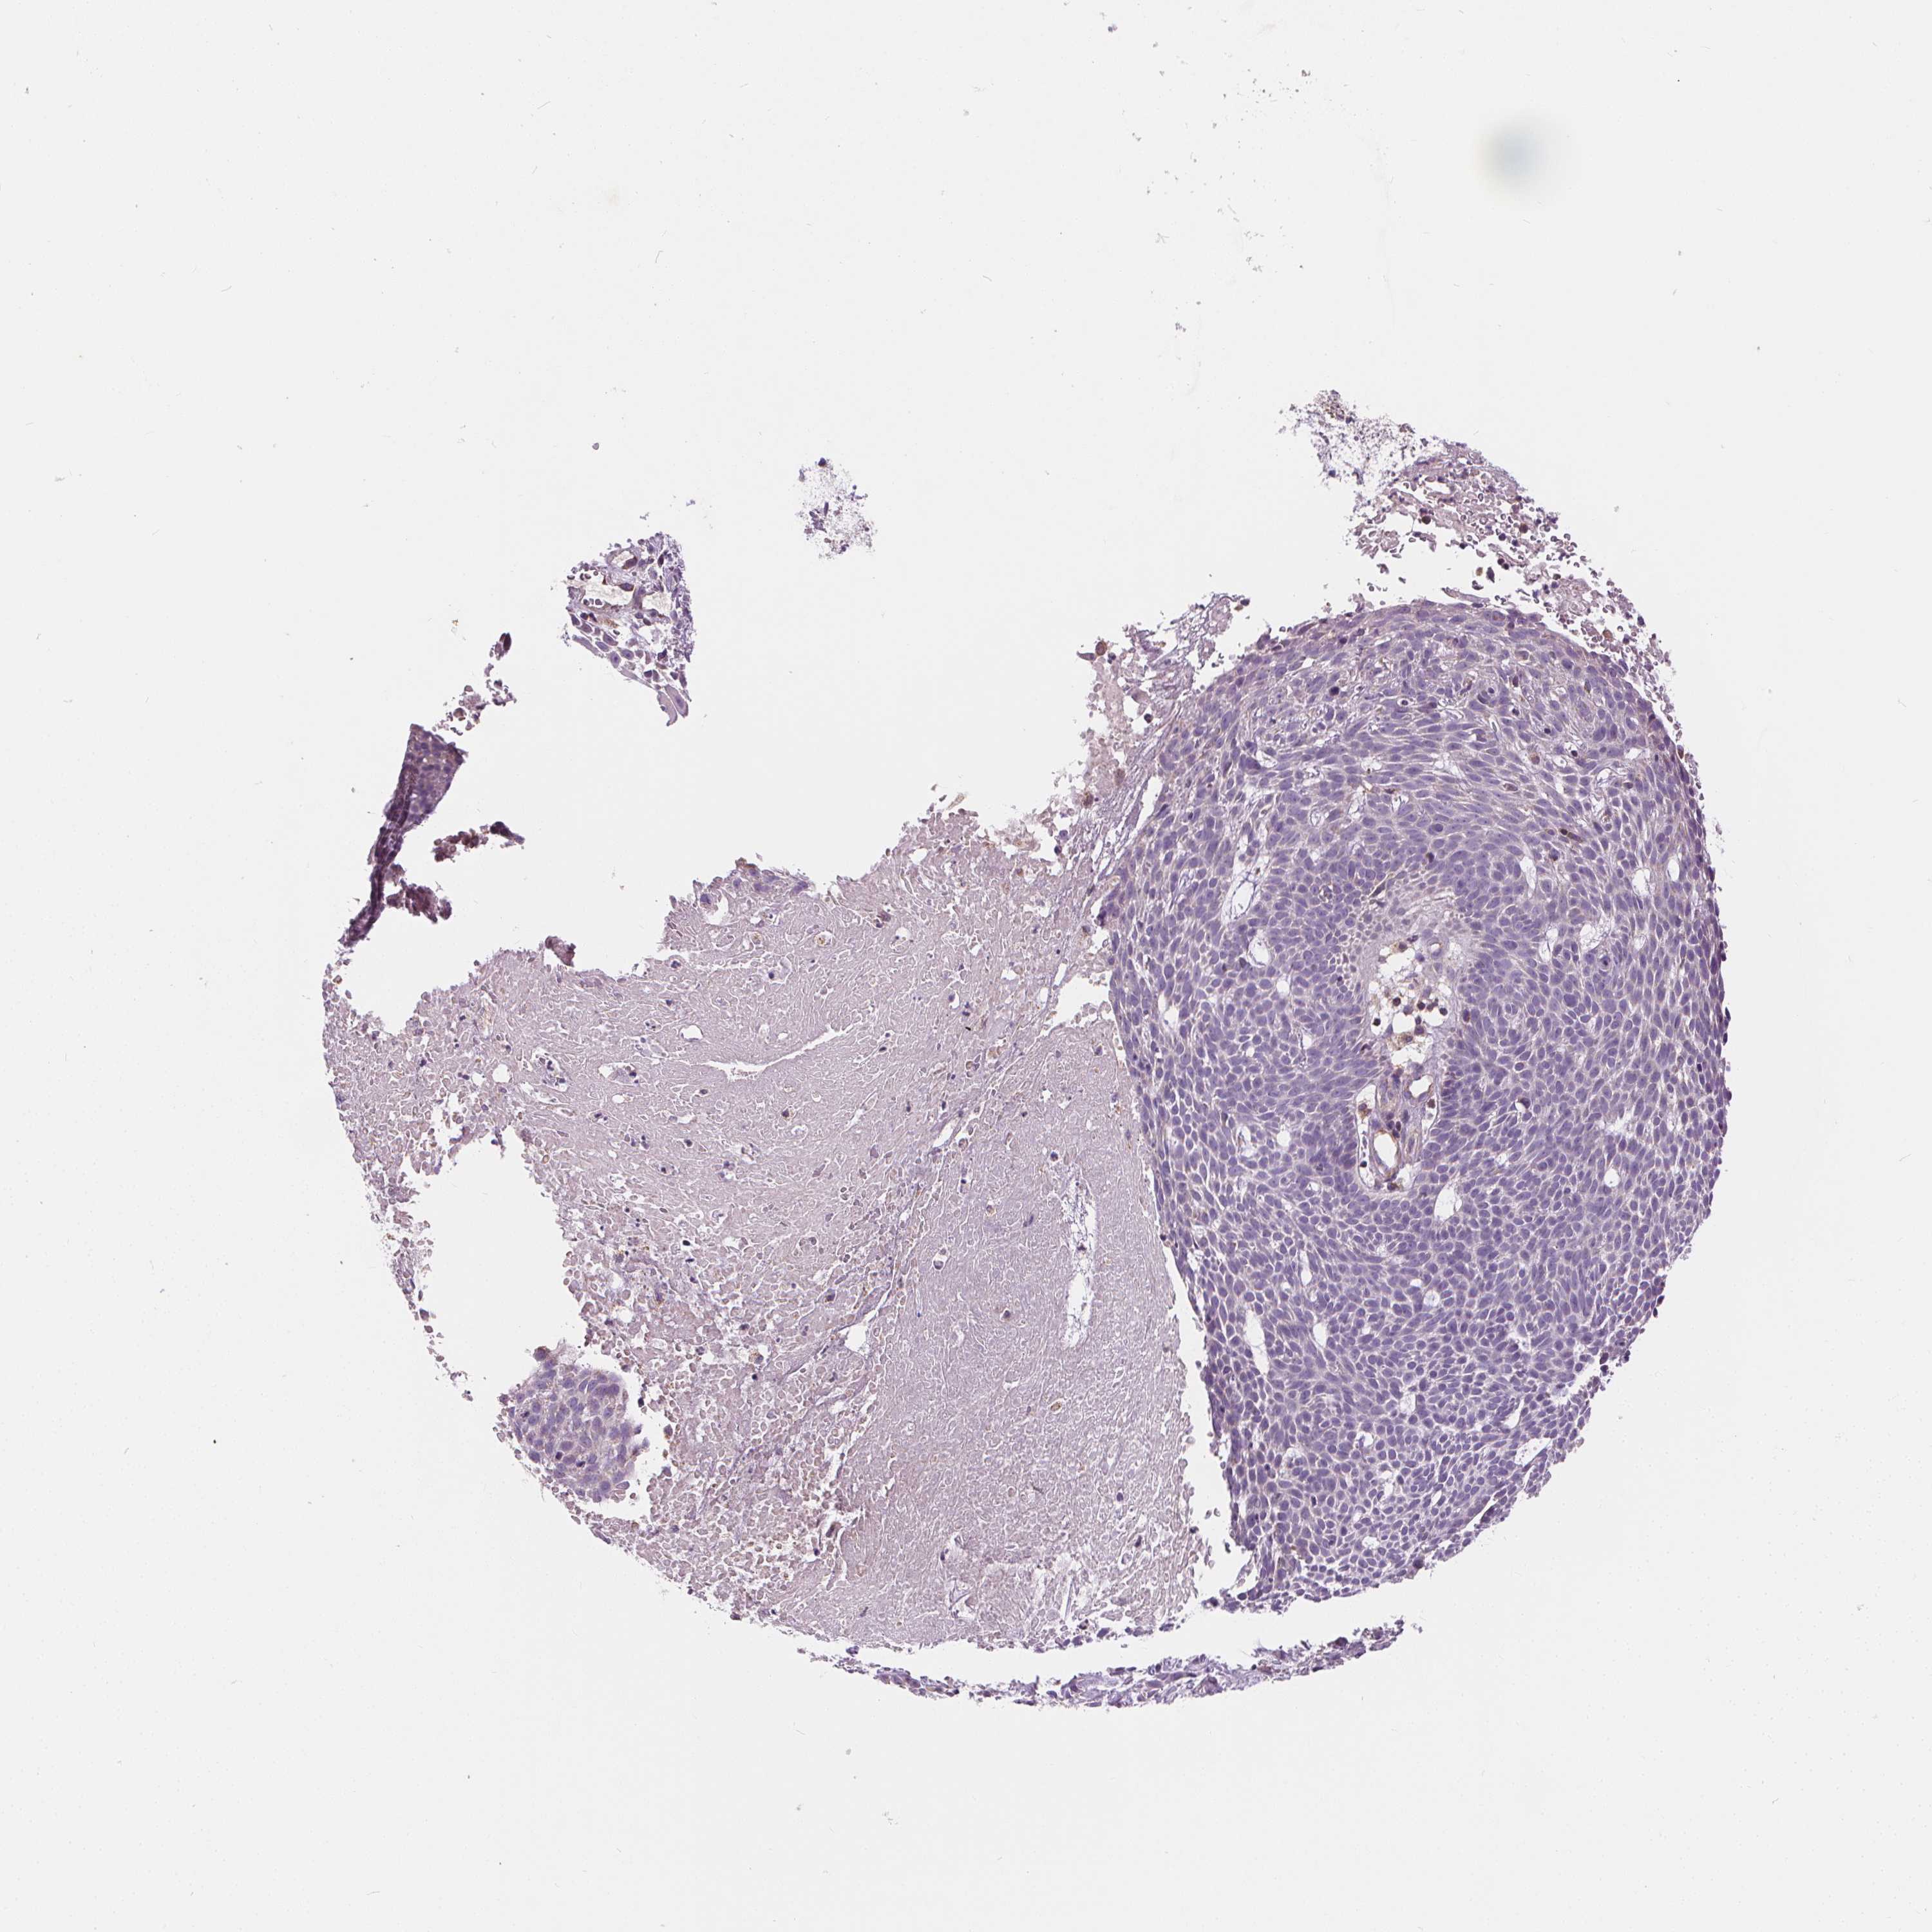

CANCER SKIN CANCER Show tissue menu

Basal cell and squamous cell cancer

SKIN CANCER - Protein expressioni

A mouse-over function shows sample information and annotation data. Click on an image to view it in a full screen mode. Samples can be filtered based on level of antibody staining by selecting one or several of the following categories: high, medium, low and not detected. The assay and annotation is described here.

Each image is clickable and will lead to virtual microscopy that enables deeper exploration of all samples and also displays staining intensity scores, fraction scores and subcellular localization as well as patient and tissue information for each sample.

Antibody HPA068647

Staining

High

Medium

Low

Not detected

Intensity

Strong

Moderate

Weak

Negative

Quantity

>75%

75%-25%

<25%

None

Location

Nuclear

Cytoplasmic/membranous

Cytoplasmic/membranous,nuclear

Basal cell carcinoma

Squamous cell carcinoma, NOS